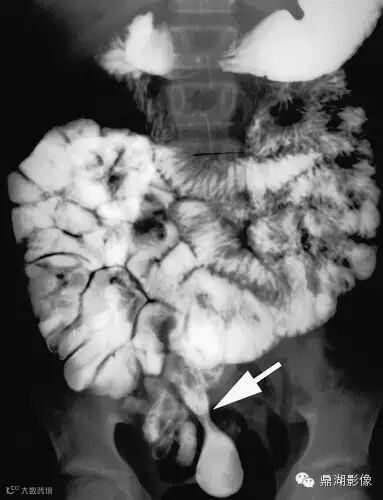

Meckel憩室钡餐:11岁女孩腹痛并贫血,回肠末端狭长Meckel憩室,背离肠系膜方向,可见较细的颈部(箭)